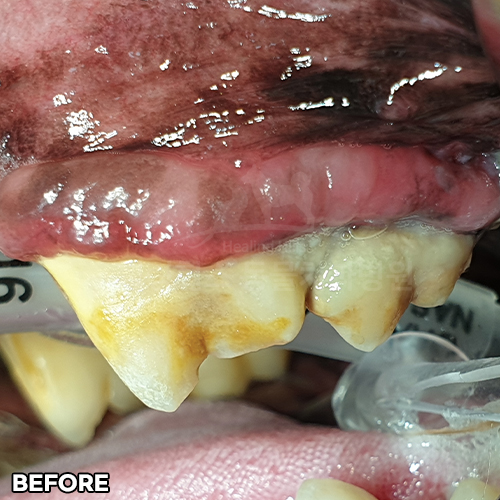

[강아지 치주염 치료 후 2주 경과]

[심한 치주염 치료 후 2주 경과]